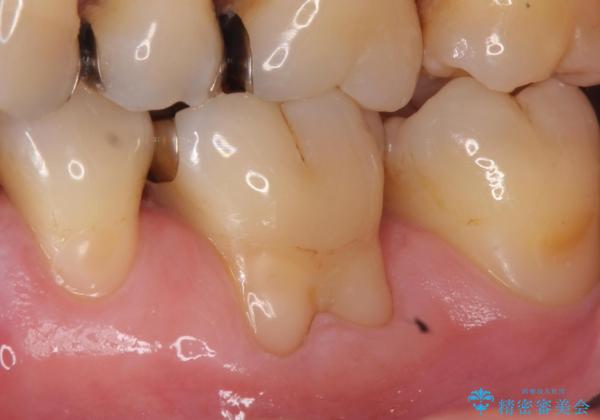

歯根の分岐部よりも根尖側の頬側面が露出している状態でしたが、露出部位を分岐部までに抑えることができました。

しみる症状も改善され、大変喜んでいただけました。

術後は歯肉が下がらないよう経過を追っていきます。